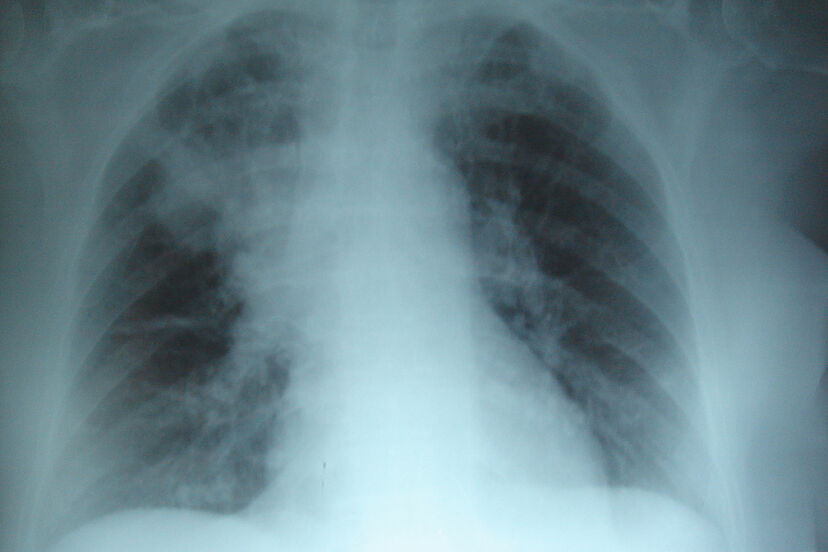

La fibrosis quística (FQ) es una enfermedad crónica y hereditaria, que produce generalmente la degeneración del sistema digestivo y del sistema respiratorio.

En realidad, esta alteración genética, solo afecta las zonas del cuerpo que producen secreciones tales como los pulmones, el páncreas, hígado y el sistema reproductivo

La fibrosis quística provoca una obstrucción en los canales que transportan dichas secreciones que terminan convirtiéndose en infecciones graves.

- Tos persistente que produce moco espeso

- Infecciones pulmonares recurrentes.